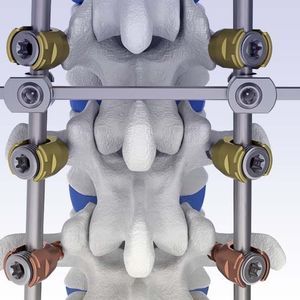

Sistemas de osteosíntesis vía posterior

... Sistema de fijación de la columna vertebral Quantum El Quantum® Spinal Fixation System permite crear una construcción rígida en la columna vertebral toracolumbar mediante tornillos pediculares, casquillos de bloqueo, varillas, conectores ...

... torácicas, lumbares y sacras (L5-S1) sirven para estabilizar los segmentos vertebrales. Uso : Se implanta con un abordaje posterior por un médico especialista. Material : Ti6Al4V-Eli está hecho de aleación. Características : Estructura ...

... 1. Fractura vertebral2. Luxación3. Escoliosis4. Deformidad Cifótica5. Deformidad discogénica6. Estenosis espinal ...

... BDyn es un sistema de estabilización dinámica posterior diseñado para una implantación entre la vértebra torácica T10 y el sacro S1. La barra dinámica BDyn se compone de un cojín de silicona, que permite reducir las cargas ...